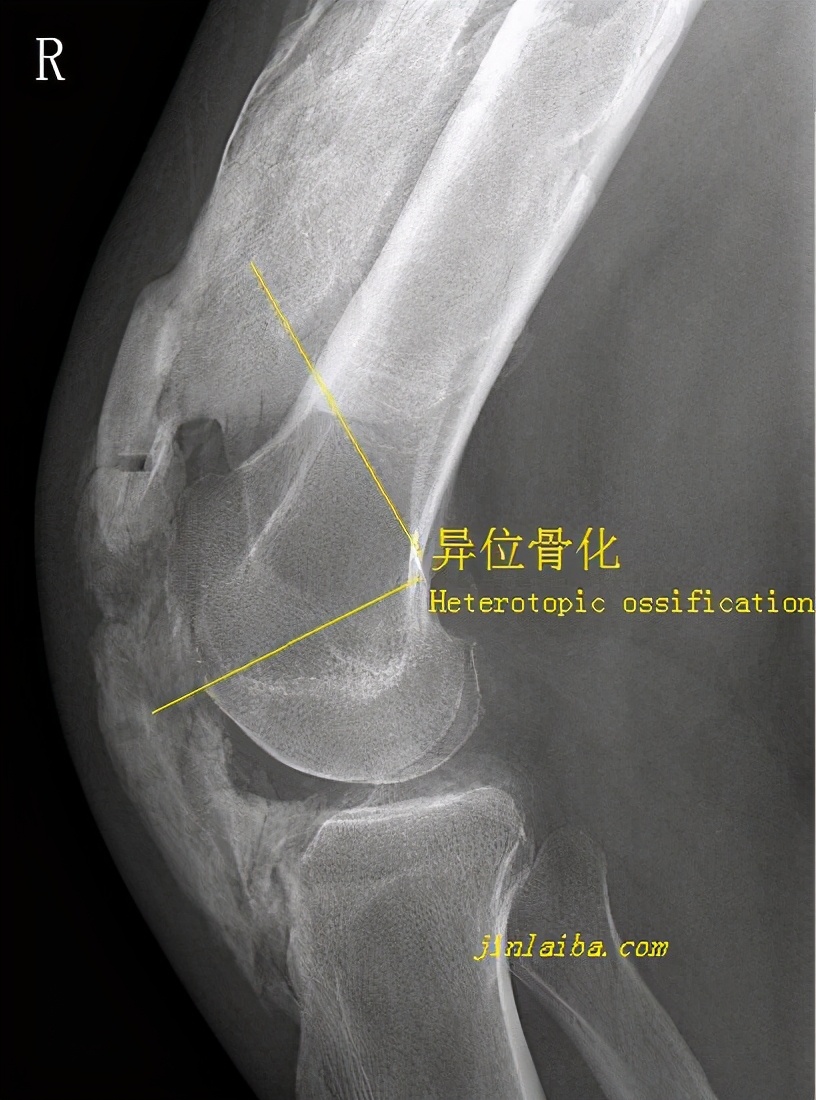

可能引发肘关节僵硬的原因有很多,软组织挛缩、关节游离体、异位骨化、骨骼退化、撞击性纤维化、关节面畸形......上面诸多因素之中,或多或少都与创伤有关。因创伤引发的肘关节僵硬可以通过非手术方法进行治疗,但如果非手术方法效果不佳,则可根据情况实施手术治疗。肘关节僵硬的手术手段与导致肘关节僵化的原因有关,比较常见的有软组织松解、异位骨化的清除、流离体和骨赘的摘除、关节成形术、关节囊切开术、肘关节置换术......手术手段的选择既与引发肘关节僵化的原因有关,也与患者的身体状况及主观意愿有关。就肘关节僵硬的术后康复而言,其核心目标有3个:一是愈合,二是恢复关节活动范围、避免粘连,三是恢复肌肉力量。